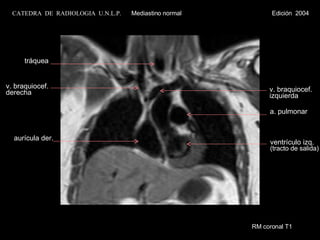

RM coronal T1 aurícula der. a. pulmonar ventrículo izq. (tracto de salida) v. braquiocef. derecha v. braquiocef. izquierda tráquea CATEDRA  DE  RADIOLOGIA  U.N.L.P.   Mediastino normal  Edición  2004

RM coronal T1aurícula der. a. pulmonar ventrículo izq. (tracto de salida) v. braquiocef. derecha v. braquiocef. izquierda tráquea CATEDRA DE RADIOLOGIA U.N.L.P. Mediastino normal Edición 2004